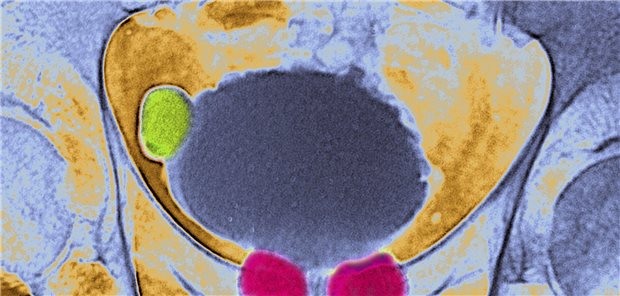

Themenseite Prostata-Hyperplasie

Themenseite - Prostata-Hyperplasie

Benignes Prostatasyndrom